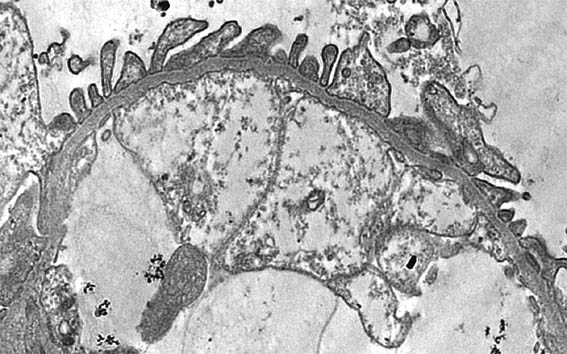

Figure 6. EM, original magnification X4,000.